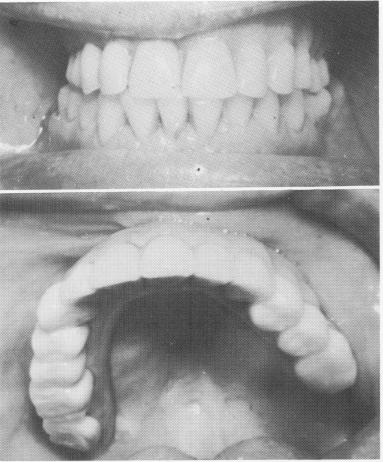

Fig. 12-82. The palateless implant denture is ready to be inserted after the healing is complete.

Fig. 12-83. The palateless denture is implant-borne and never touches the fibromucosal tissue.

The sutures are removed about 1 week later. Any necessary adjustments with the fit and occlusion of the temporary denture are made. When all healing has taken place (Fig. 12-82), the final palate-less implant denture is processed. The cast metal superstructure is placed over the implant posts, and a wax bite registration of centric relationship is taken. The superstructure is picked up with an elastic impression. The wax-up of the maxillary denture with acrylic teeth is tried in the mouth. (If the patient also has an edentulous lower jaw, the lower wax-up should be accomplished at the same time.) The completed denture is inserted and balanced (Fig. 12-83). A Panorex shows the finished case (Fig. 12-84).

3 Upper palateless implant denture ready for insertion after healing

4 Palateless denture is implant borne & not touches fibromucosal tissue